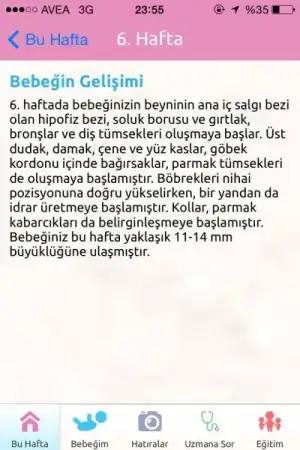

Ben onu da göremedim canım ya.. Çok istemiştim bugün ama olmadı. Haftaya gel dedi. Kalp atışlarını duycağım anı iple çekiyorum. İçimde benden bi parça var bu beni çook heycanlandırıyo

Tamam canım şimdi hatırladım. Medical parka gitmiştin dimi. Ordaki ultrasondan görememiştin. Olsun bu hafta görürsün merak etme 6000lerde görünüyo karından. Geç olsun güç olmasın canım :)